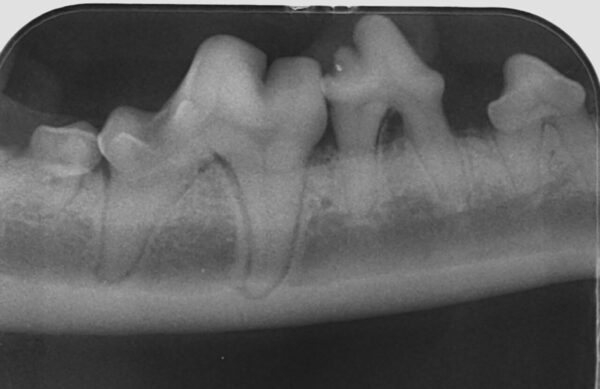

Además de permitirnos evaluar el grado de enfermedad periodontal, también hace posible seleccionar el mejor tratamiento en función de su patología y las posibles complicaciones, como las fracturas mandibulares iatrogénicas en perros de talla pequeña con enfermedad periodontal PD4 (imágenes 10 y 11).